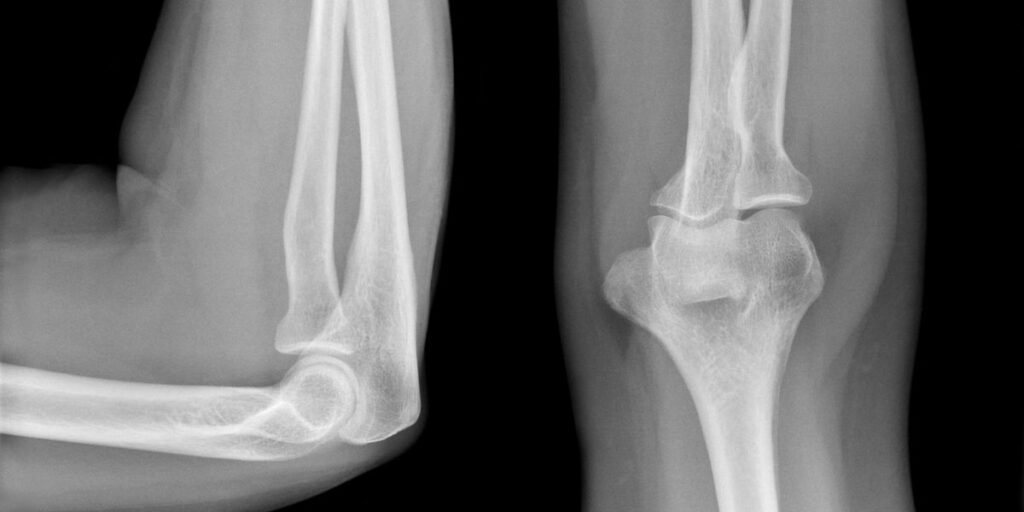

L’RX Gomito, conosciuto anche come radiografia del gomito, è un esame radiologico che utilizza i raggi X per ottenere immagini dettagliate delle ossa del gomito. Questa procedura permette ai medici di individuare lesioni, fratture e altre anomalie, fornendo una visione completa dell’articolazione. Al Poliambulatorio S-Medical Group di Sora, ci avvaliamo di tecnologie avanzate e specialisti esperti per offrire un servizio diagnostico di altissima precisione.

Durante un esame RX Gomito, il paziente viene guidato da un tecnico radiologo a posizionare il braccio in modo da ottenere immagini dettagliate e complete. Presso il Poliambulatorio S-Medical Group di Sora, l’esame si svolge in pochi minuti e non richiede preparazioni particolari. Le proiezioni radiografiche ottenute vengono poi analizzate dai nostri radiologi per individuare eventuali problematiche e per fornire una diagnosi precisa.

Grazie a un RX Gomito è possibile visualizzare chiaramente le strutture ossee che compongono l’articolazione, tra cui ulna, radio e omero. Questo esame permette di identificare con precisione:

• Fratture e microfratture

• Lussazioni o dislocazioni

• Segni di artrite o artrosi

• Calcificazioni e depositi minerali anomali

• Alterazioni ossee dovute a condizioni degenerative

Il Poliambulatorio S-Medical Group di Sora si avvale di macchinari all’avanguardia, garantendo immagini nitide e dettagliate per una valutazione accurata.